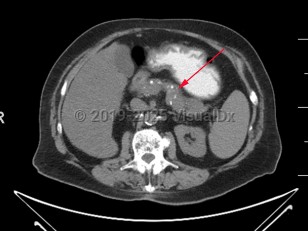

Imaging Studies image of Chronic pancreatitis - imageId=7877567. Click to open in gallery.  caption: '<span>Axial CT image demonstrates numerous coarse calcifications within the pancreas, consistent with chronic pancreatitis.</span>'

Axial CT image demonstrates numerous coarse calcifications within the pancreas, consistent with chronic pancreatitis.